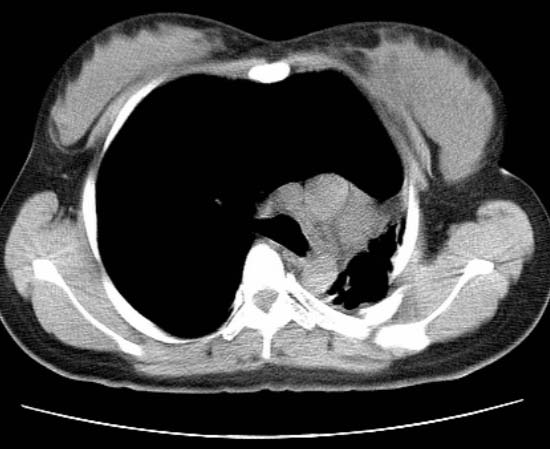

标题: CT25648:求教:是肺发育不全还是结核?

女  20岁。一月前咳血,诊“肺结核”抗痨治疗一月后,咳血停止,现复查。病人精神好。前后ct片对比未见明显变化。既往体检“正常”

1)考虑左肺结核并肺不张、支气管扩张。2)纵隔疝。

以前体检正常只能考虑左肺结核并肺不张、支气管扩张。2)纵隔疝。

考虑左肺结核,左肺毁损,纵膈左偏,既往体检正常不可靠,tb一个月也不会这个样子的,有钙化,应该病程较长,冰冻三尺非一日之寒!

左肺发育不全。

考虑左肺结核,左肺毁损,纵膈左偏,既往体检正常不可靠,tb一个月也不会这个样子的,有钙化,应该病程较长,冰冻三尺非一日之寒

结核,左肺毁损。